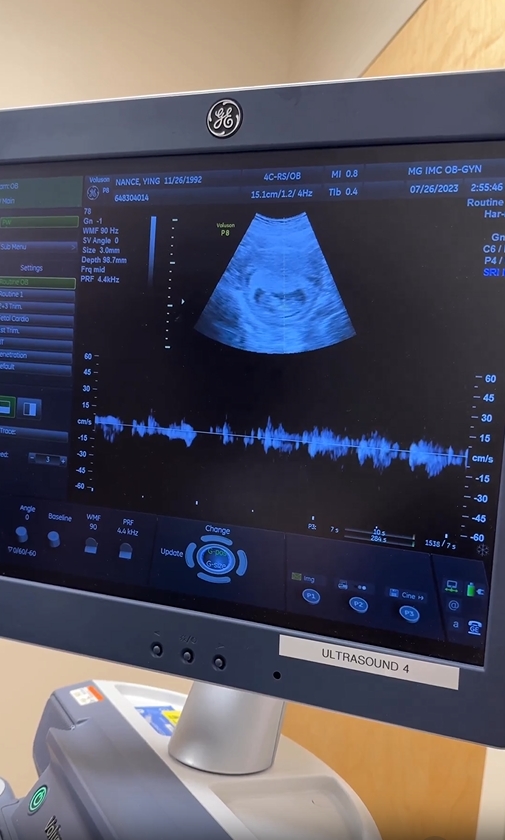

โดย หญิง พลอยชมพู ได้โพสต์คลิปโชว์ภาพอัลตราซาวด์ในครรภ์ พร้อมระบุแคปชั่นว่า “กว่าจะได้เจอหมอ ท้องจนลืมไปเเล้วว่าท้อง Baby #2 coming Feb 2024! Lizzie’s going to be a big sissy” (ลูกคนที่ 2 จะคลอดเดือนกุมภาพันธ์ 2024 น้องลิซซี่กำลังจะกลายเป็นพี่สาวแล้ว)